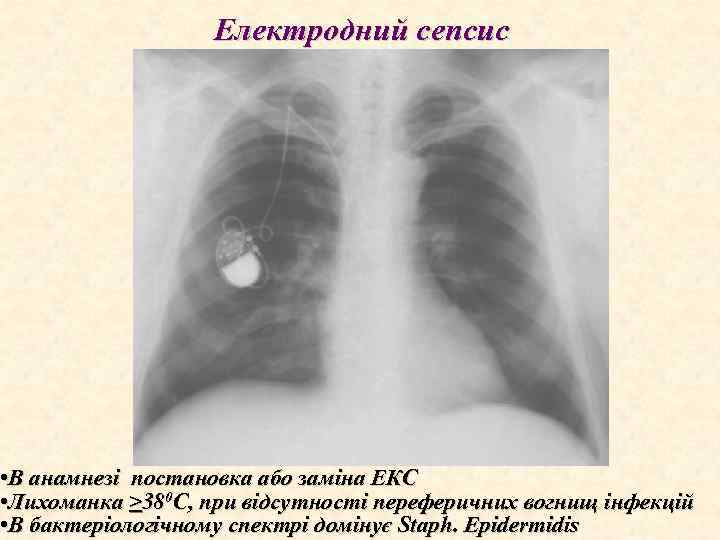

Електродний сепсис • В анамнезі постановка або заміна ЕКС • Лихоманка >380 С, при відсутності переферичних вогнищ інфекцій • В бактеріологічному спектрі домінує Staph. Epidermidis